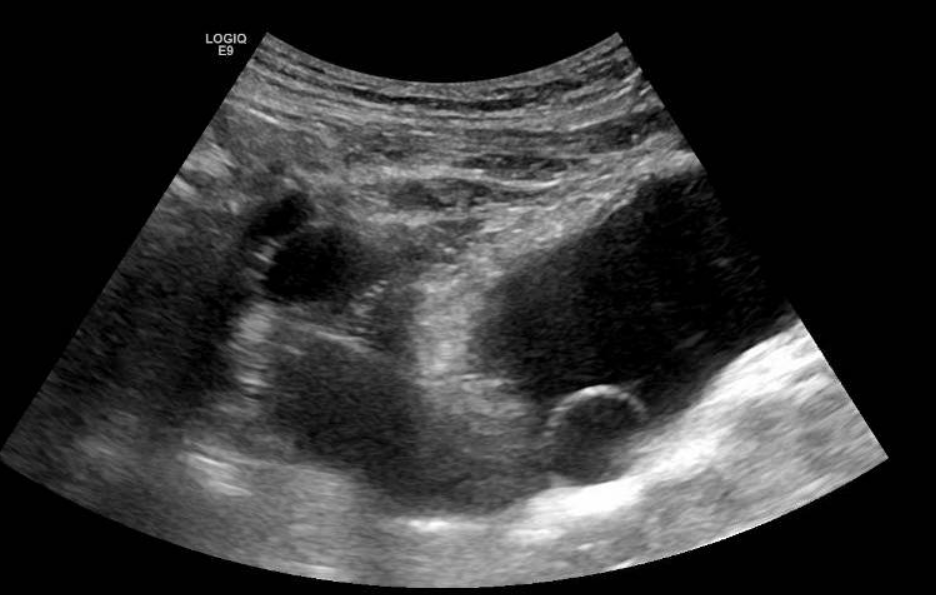

Se solicita ecografía abdominal donde se observa el riñón derecho de tamaño normal, con adelgazamiento parenquimatoso difuso secundario a ureterohidronefrosis severa que se extiende hasta la unión vesicoureteral, donde se visualiza una lesión anecoica intravesical, en relación con el ureterocele ya conocido, que condiciona el cuadro obstructivo.